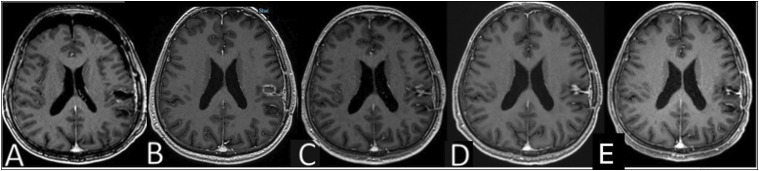

Case reports: Case 1 discusses a 41-year-old male with GBM, highlighting the challenges of differentiating tumor progression from treatment-induced pseudoprogression. Case 2 discusses a 45-year-old female with brain metastatic malignant melanoma, presenting radiological evidence of progressive disease while undergoing nivolumab treatment. Case 3 discusses a 37-year-old male with GBM, where radiological evidence indicates progressive disease while receiving pembrolizumab treatment.

Management and outcomes: In case 1, we discussed the challenges of distinguishing true tumor progression from treatment-induced pseudoprogression, leading to the continuation of the same treatment due to pseudoprogression. In case 2, post-surgery pathology revealed radionecrosis and treatment-related changes, guiding the continuation of nivolumab therapy. Case 3 involved a pathologically confirmed progression, and the patient received best supportive care due to his performance status.